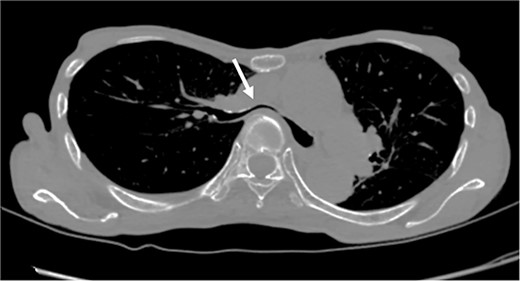

Based on these imaging tests, surgery for oropharyngeal cancer caused breathing difficulties due to a leftward shift of the trachea. The sternum’s depression led to severe narrowing of the right main bronchus, and age-related factors added to the respiratory distress. We performed a Nuss procedure for PE repair to release the stenosis of the right main bronchus surgically. As thoracoscopy revealed a depressed sternum, we corrected the sternal depression by sternal elevation using two pectus bars. Postoperative chest CT showed improvement in the sternal depression (HI:4.6, Fig. 3B) and right main bronchial stenosis (Fig. 4B). Furthermore, shortness of breath was relieved postoperatively.

Pre- (A) and postoperative (B) CT findings: the Nuss procedure improved the chest wall and right main bronchus stenosis, and reduced HI from 8.9 to 4.6.